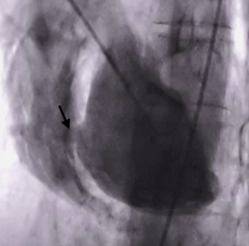

Ventriculografia: ao injetar contraste há a presença da comunicação (seta preta) e observamos contraste no VD: